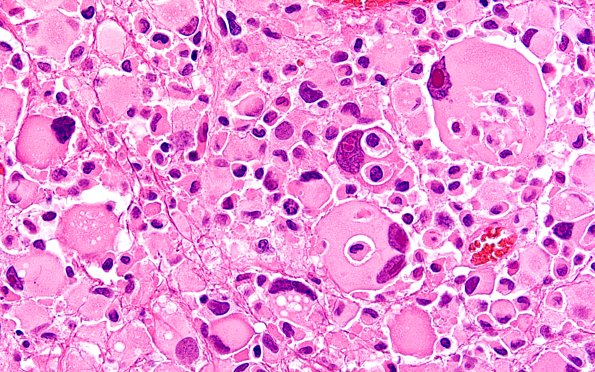

Pleomorphic Xanthoastrocytoma (PXA)

22B16 PXA (Case 22) H&E B2 60X 13

Additional examples of possible emperipolesis? (H&E)